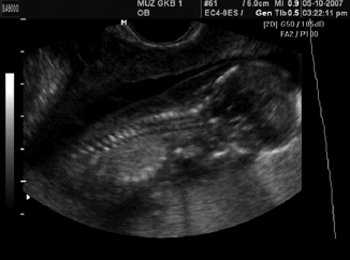

Пациентка А., 27 лет, паритет 2/1, поступила в роддом для пренатальнои диагностики в связи с выявленным ультразвуковым маркером хромосомных аномалий (увеличение ТВП до 5,6 мм) (рис. 1). Срок беременности составил 13 нед 6 дней. Выполнена трансабдоминальная хорионбиопсия, диагностирована трисомия 21. Повторно пациентка поступила через 4,5 нед (срок беременности 18 нед 4 дня) для прерывания беременности по медицинским показаниям.

Ультразвуковые исследования выполнялись на аппарате SonoAce-8000 Ex (компании Medison) с применением абдоминального конвексного датчика 3-7 МГц и внутриполостного конвексного датчика 4-9 МГц.

По данным аутопсии диагноз общего предсердно-желудочкового канала полностью подтвержден (верифицирована полная форма порока).

Во втором наблюдении при исследовании дуги аорты оказалось, что визуализировать дугу на всем протяжении невозможно (рис. 8). Определялись восходящая аорта и отходящие от нее плечеголовной ствол и левая сонная артерия. Затем изображение дуги аорты отсутствовало и, далее, определялась дистальная часть дуги, левая подключичная артерия и нисходящая аорта (рис. 9).